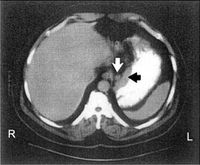

صورة بالتصوير الطبقي المحوري تبين كتلة ورمية في المعدة (السهم الأسود)، وعقدة لمفية متضخمة مرافقة (السهم الأبيض)

يستخدم التصوير الطبقي المحوري CT-SCAN (الصورة ـ1) والتصوير بالأمواج فوق الصوتية ultrasound و الرنين المغنطيسي MRI scan لتشخيص النقائل وتحديد مرحلة الورم.